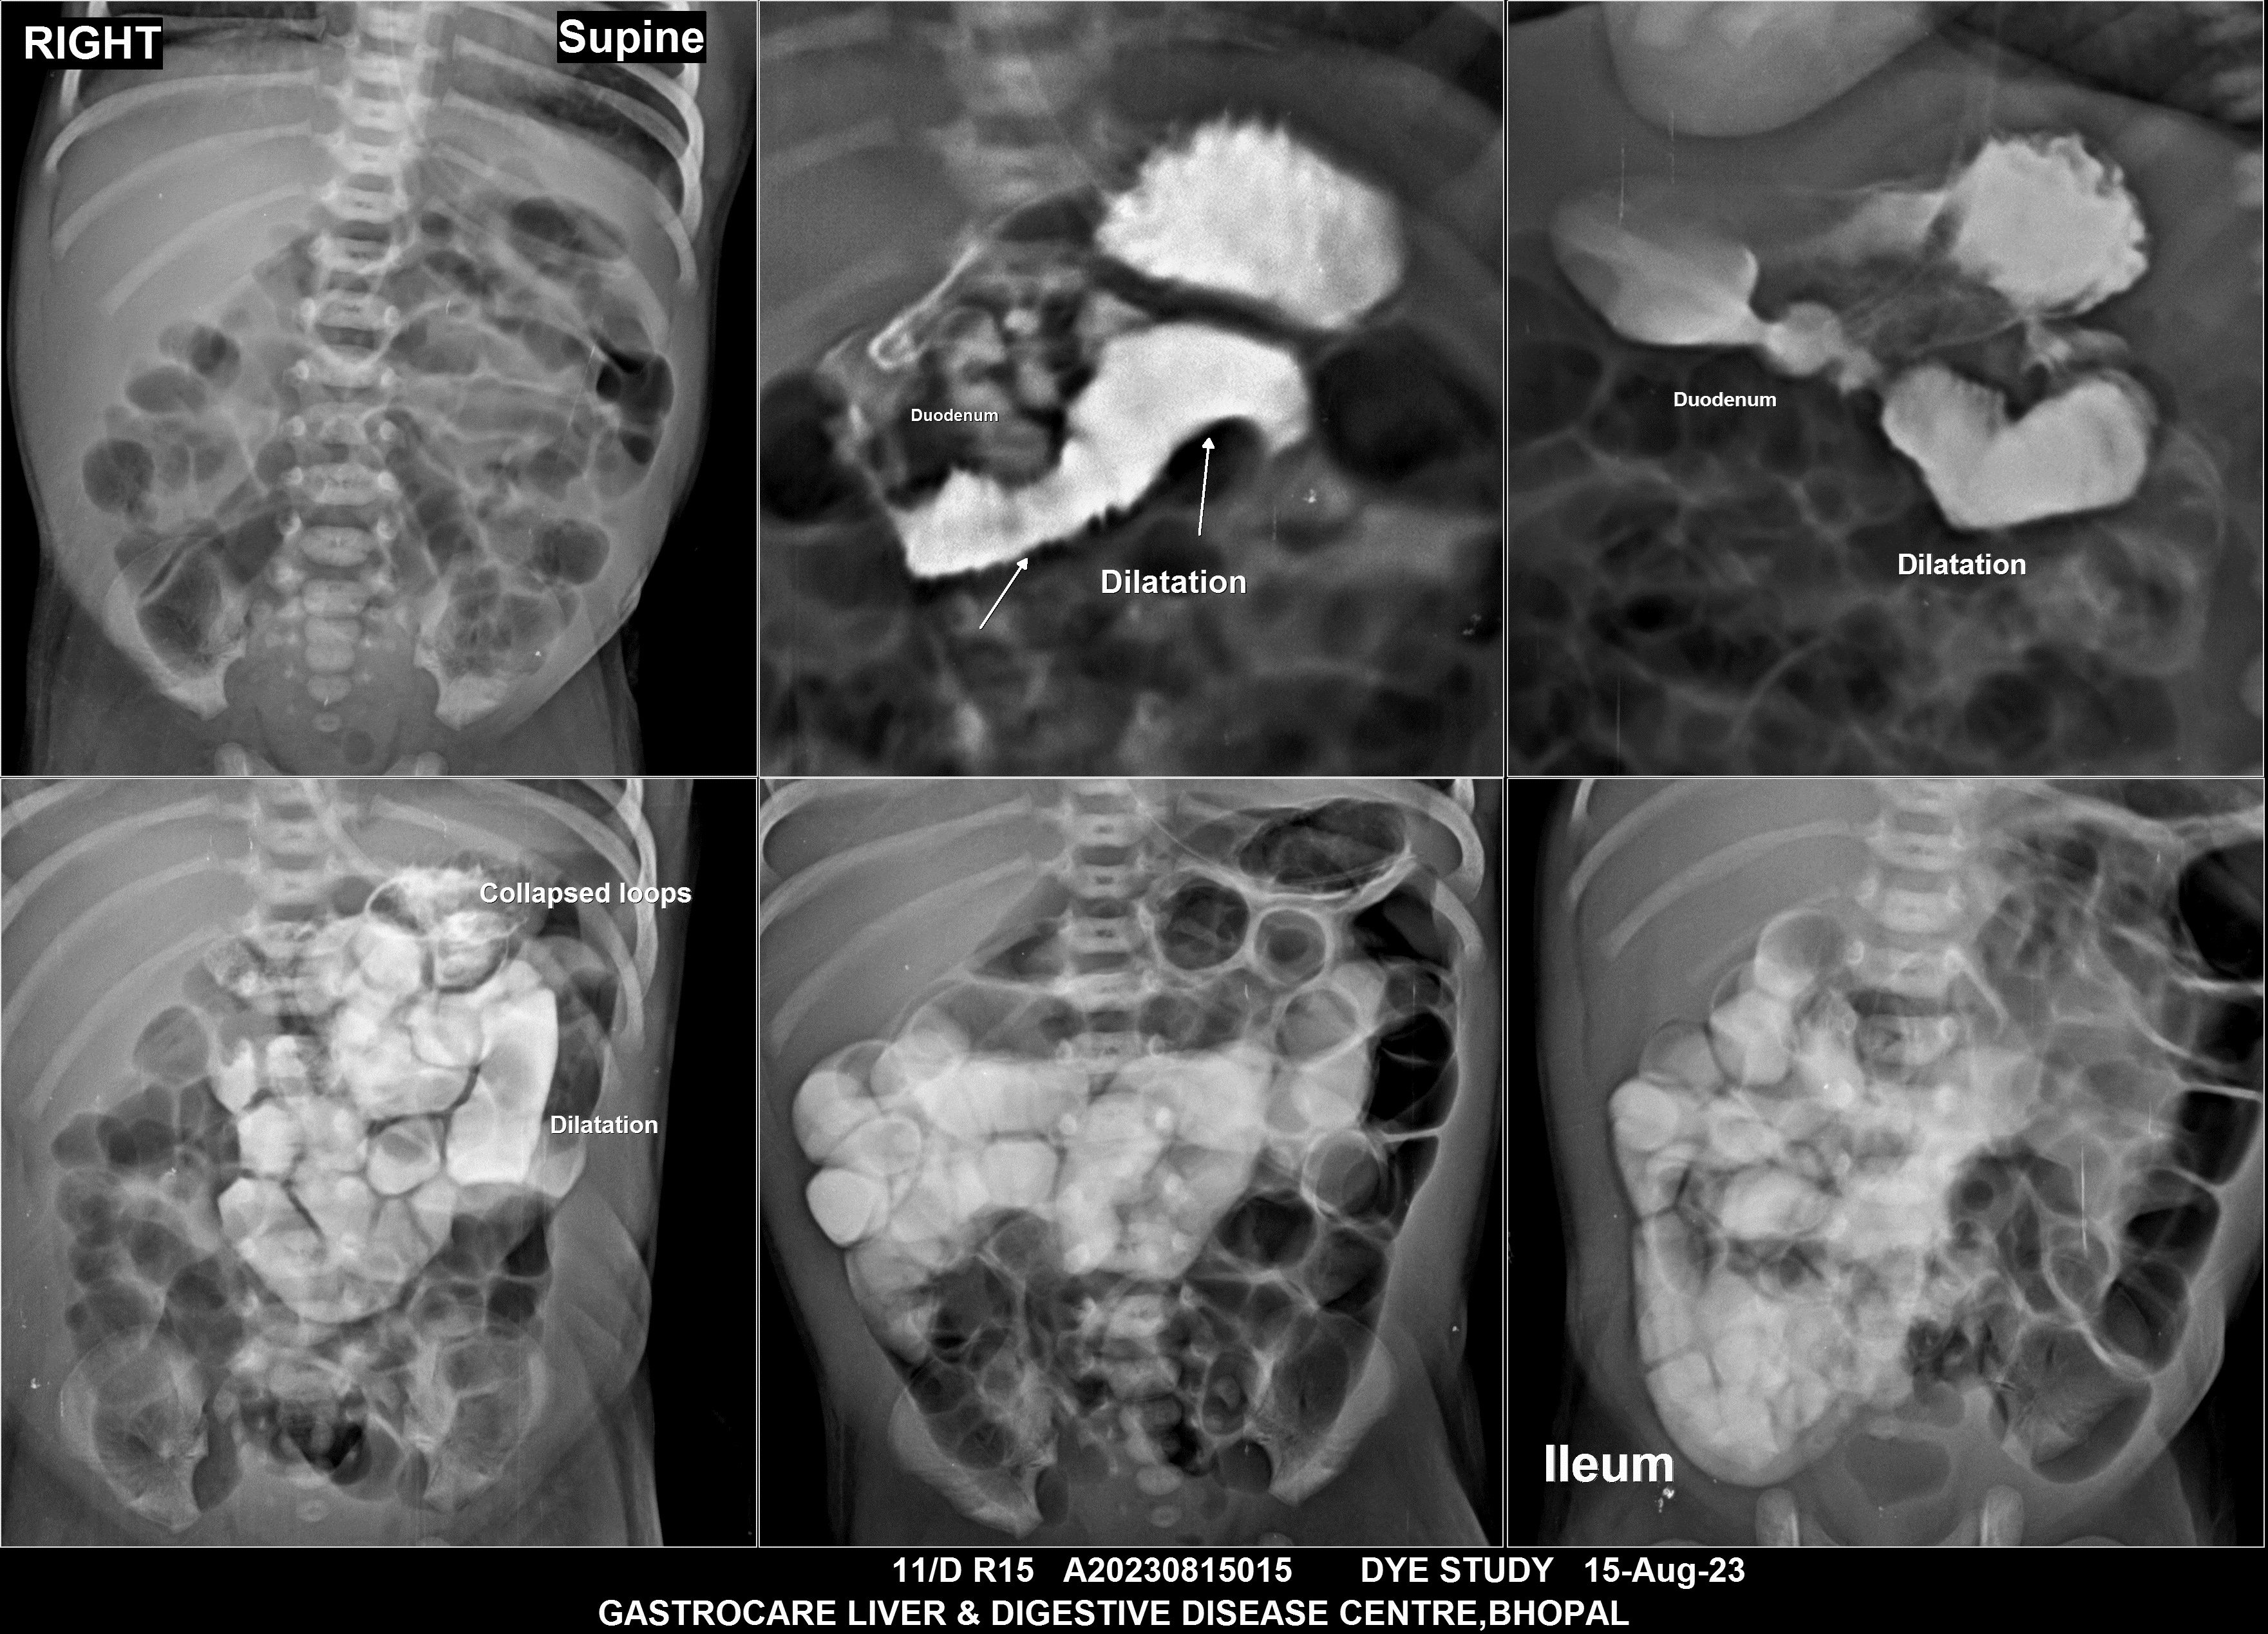

Section: BAM Total: 43 images

BaM Enteroclysis Loopogram BaE Fistulogram Urethrogram HSG